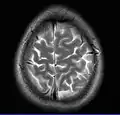

Cross-sectional T1-weighted MRI of a healthy human brain acquired with an ultra high-field MR of 7 Tesla field strength